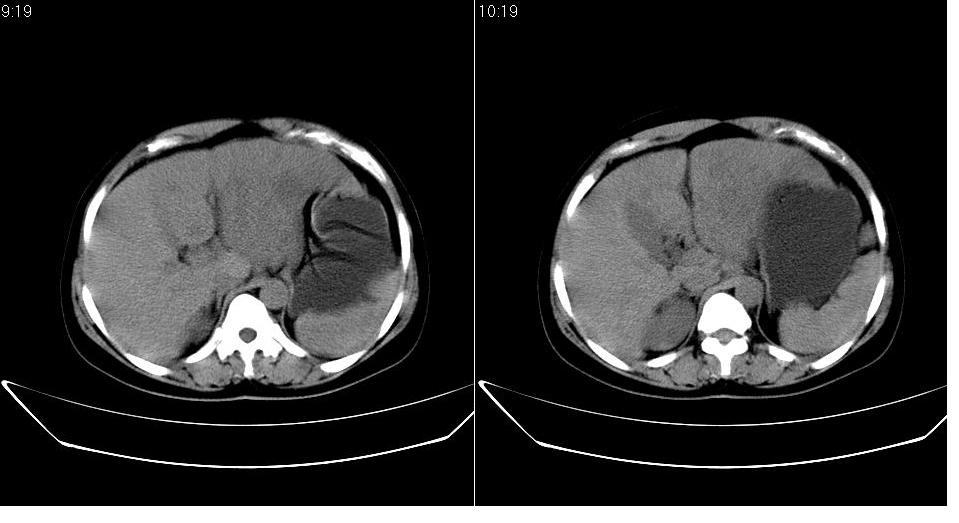

女 36岁,腹痛月余,b超提示肝左叶占位,腹水。

肝脏左叶明显增大,各叶比例失调,左叶实质内不均匀低密度影,似乎有肝内胆管的扩张,没有增强实在不好判断,不知患者肝功能是否正常,我觉得象胆管细胞癌。

支持!且患者肝门部有淋巴结转移。

1)考虑肝左叶肝癌;建议行进一步检查。2)肝硬化,脾稍大。3)双侧少量胸腔积液。

肝癌可能性大,建议增强